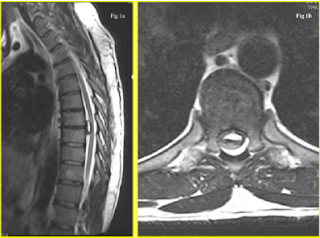

A working diagnosis of a potential space occupying lesion (SOL) in the thoracic region, causing mechanical compression of the spinal cord and/or nerve root(s), was suspected. An immediate MRI scan was arranged, which revealed a large mass causing the ventral effacement of CSF flow / signal at the T7- T8 level. His T2 weighted MRI images are illustrated in (Figure 1a & 1b). The differential diagnosis included disc herniation and other benign intra-axial neoplasms (i.e. meningioma and schwannoma). A CT scan was requested to further understand the lesion, study the extent of calcification / bony, and the intradural involvement (if any). The key CT sagittal and axial images are depicted in (Figure 2a & 2b). From these, the diagnosis narrowed down to a large central calcified TDH, following a discussion at the multi-disciplinary team (MDT) meeting.